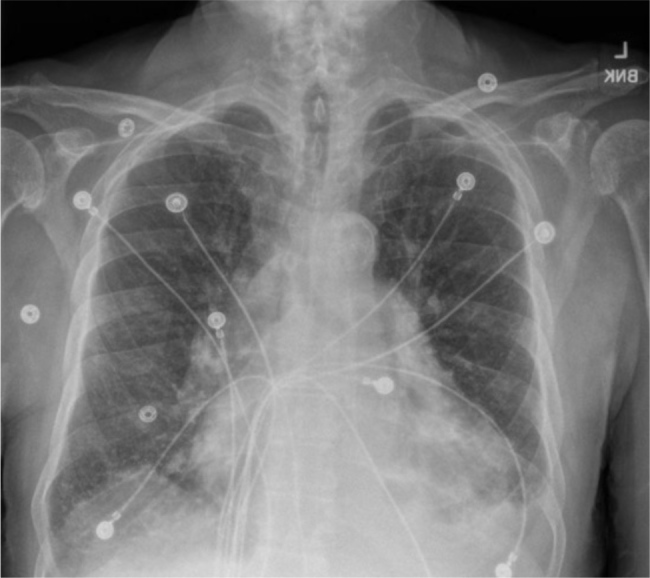

Minoxidil is a direct-acting vasodilator that reduces systemic vascular resistance by opening adenosine triphosphate (ATP)-sensitive potassium channels, leading to arteriolar smooth muscle vasodilation. While commonly prescribed for resistant hypertension and androgenic alopecia, minoxidil is associated with fluid retention, and in rare cases, pericardial effusion that can progress to cardiac tamponade. In this report, we present a case of an 81-year-old male with a history of chronic kidney disease (CKD) who developed cardiac tamponade while on chronic minoxidil therapy for hypertension. He presented with progressive dyspnoea, lower extremity oedema, and fever. Imaging revealed an enlarged cardiac silhouette, and a confirmatory echocardiogram demonstrated a pericardial effusion with right ventricular collapse. The patient underwent urgent pericardiocentesis, yielding 545 ml of pericardial fluid. Infectious, malignant, and autoimmune aetiologies were ruled out, and minoxidil was identified as the likely cause. Following discontinuation of minoxidil, the patient's symptoms completely resolved, with no recurrence at 1-month follow-up. In addition, we reviewed 26 previously reported cases of minoxidil-induced pericardial effusion and/or cardiac tamponade, 17 of which are summarized in this report. This case demonstrates the rare but potentially fatal complication of therapy and emphasizes the importance of early detection and clinical vigilance, particularly in vulnerable populations such as patients with CKD.

Abstract Image